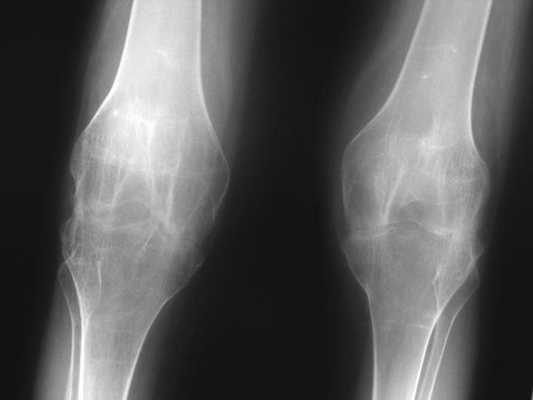

Стадии артрита коленного сустава на рентгене.